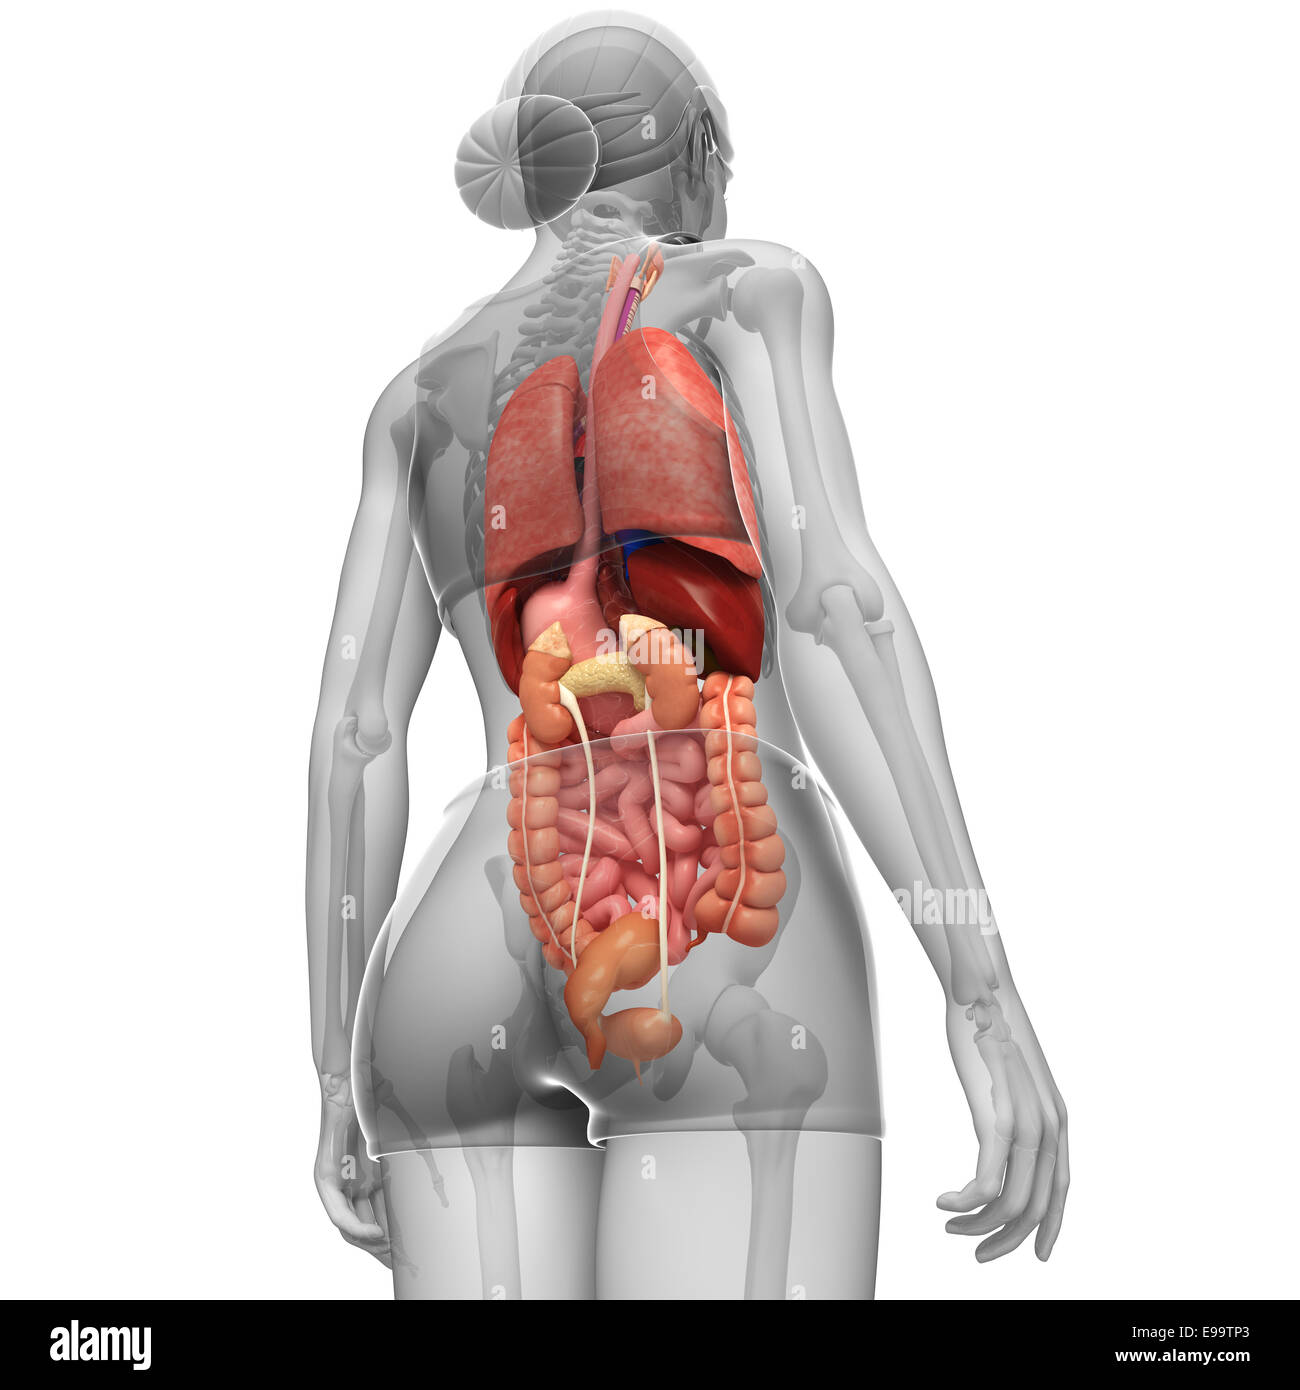

Anatomy Of Internal Organs Female – Organ Anatomy Female Anatomy …

Right Side Women’s Body Human Body Organs / Human Anatomy And …

Female Body Organs Diagram Anatomy | MedicineBTG.com

Human Anatomy Picture Organs Female Human Body Diagram Of Organs See …

Female Human Organs Diagram | MedicineBTG.com

Ilustración del sistema digestivo femenino vista posterior Fotografía …

Female Abdominal Anatomy Images . Female Abdominal Anatomy Images …

Female Abdominal Anatomy Pictures – koibana.info | Anatomy organs …

Internal Organs Adult Female Front And Back View Stock Photo – Download …

Illustration Of Female Internal Organs Photograph by Science Source

Illustration Of Female Internal Organs Photograph by Science Source

Human Female Organ Diagram . Human Female Organ Diagram Colorful Human …

3dsmax human female internal organs

Female Internal Organs, Artwork Photograph by Roger Harris

Human Female Internal Organs Anatomy 3D Model MAX OBJ 3DS FBX C4D LWO …

女性内脏3D模型 – TurboSquid 966689